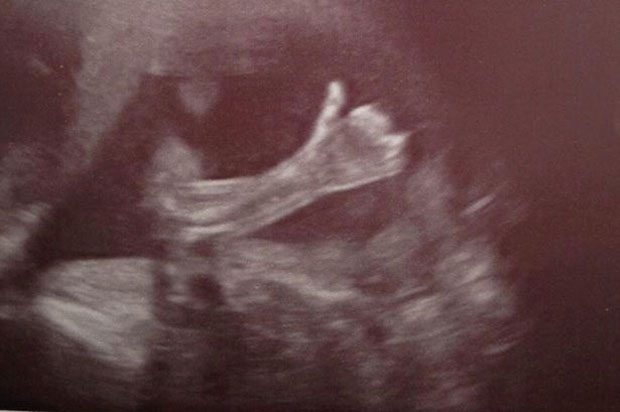

Uma imagem incomum tem chamado atenção na web. Ela mostra um bebê no útero acenando o polegar como se dissesse que estava tudo “ok”.

A fotografia do ultrassom surpreendeu os pais, Paul Schofield, de 31 anos, e Cheryl Stevenson, de 32 anos. Eles estavam na vigésima semana de gestação.

O casal vive em Manchester, na Inglaterra. Eles descobriram, no incidente, que estavam esperando um menino.